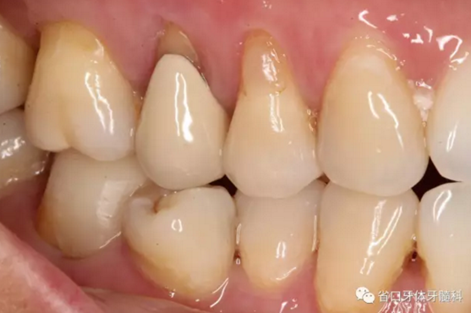

46/咬合面見殘留充填物,近中頰尖牙體缺損,缺損周圍見近中頸部繼發(fā)深齲壞,探穿髓,探痛-,叩±,松-,頰側(cè)牙齦見瘺口,頰側(cè)探及深牙周袋約5毫米。

初步診斷:46/慢性根尖周炎 牙周炎